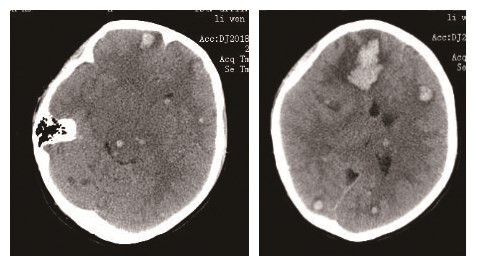

1 资料与方法患者女性,18岁,以“发热、头痛1周,加重1天”为主诉, 于2018年1月24日入院。1周前受凉后出现发热,体温最高39.9 ℃,伴寒颤、头痛、肌肉疼痛,无呼吸困难、胸闷等症状,至当地医院给予头孢、阿奇霉素静脉滴注,仍高热。3 d前出现恶心、呕吐、面部、双上肢及腹部散在皮疹。1 d前查白细胞24.8×109/L,血小板19×109/L,精神差,治疗效差,遂急诊来我院。既往体健。入院查体:嗜睡,头面部、腹部多发散在皮下出血点。双侧瞳孔等大等圆,直径约2 mm,对光反射灵敏,颈软无抵抗,双肺呼吸音清,未闻及干湿性啰音。心脏听诊无异常。入院诊断为发热待查:血流感染?白血病?入院后留取血培养、痰培养,行骨髓穿刺术。急查头颅及肺部CT见:蛛网膜下腔出血,肺部CT未见明显异常。心脏超声示:左心耳内稍高回声大小约16 mm×8 mm(血栓?);二尖瓣少量反流;三尖瓣少量反流。给予哌拉西林他唑巴坦+左氧氟沙星抗细菌治疗,帕拉米韦抗病毒,同时给予止血、输血小板、升血小板药物应用。入院36 h血培养报警:革兰阳性球菌,立即加用万古霉素1.0 g q 12 h静脉滴注,我院血培养报警后当地医院血培养结果电话回示金黄色葡萄球菌。追问病史,入院两周前有至非正规医疗机构纹眉史。入院后第3天患者昏迷,急查头颅CT,示颅内多发散在、点片状出血(图 1),给予保守治疗,继续输血小板、血浆、冷沉淀。骨穿结果回示:感染骨髓象。我院血培养回示:耐甲氧西林金黄色葡萄球菌(MRSA)。补充诊断:MRSA致血流感染,感染性心内膜炎?脑出血;血小板减少。

| 图 1 入院后第3天患者头颅CT |

金黄色葡萄球菌血流感染易导致感染性心内膜炎,其机制尚不清楚,可能与金黄色葡萄球菌毒力强,繁殖快,有高度侵袭性及粘附心内膜的能力有关。20%感染性心内膜炎患者可出现脑梗死及脑出血,所有感染性心内膜炎引起的卒中,出血占30%,脑梗死占70%[3]。引起脑出血的机制可能是:瓣膜赘生物脱落,随血流播散至全身,进入颅内则导致颅内血管堵塞,细菌繁殖,血管壁炎症反应,严重者可能血管破裂导致脑出血。该患者颅内多发点片状出血,考虑可能为瓣膜小赘生物脱落堵塞小动脉导致。